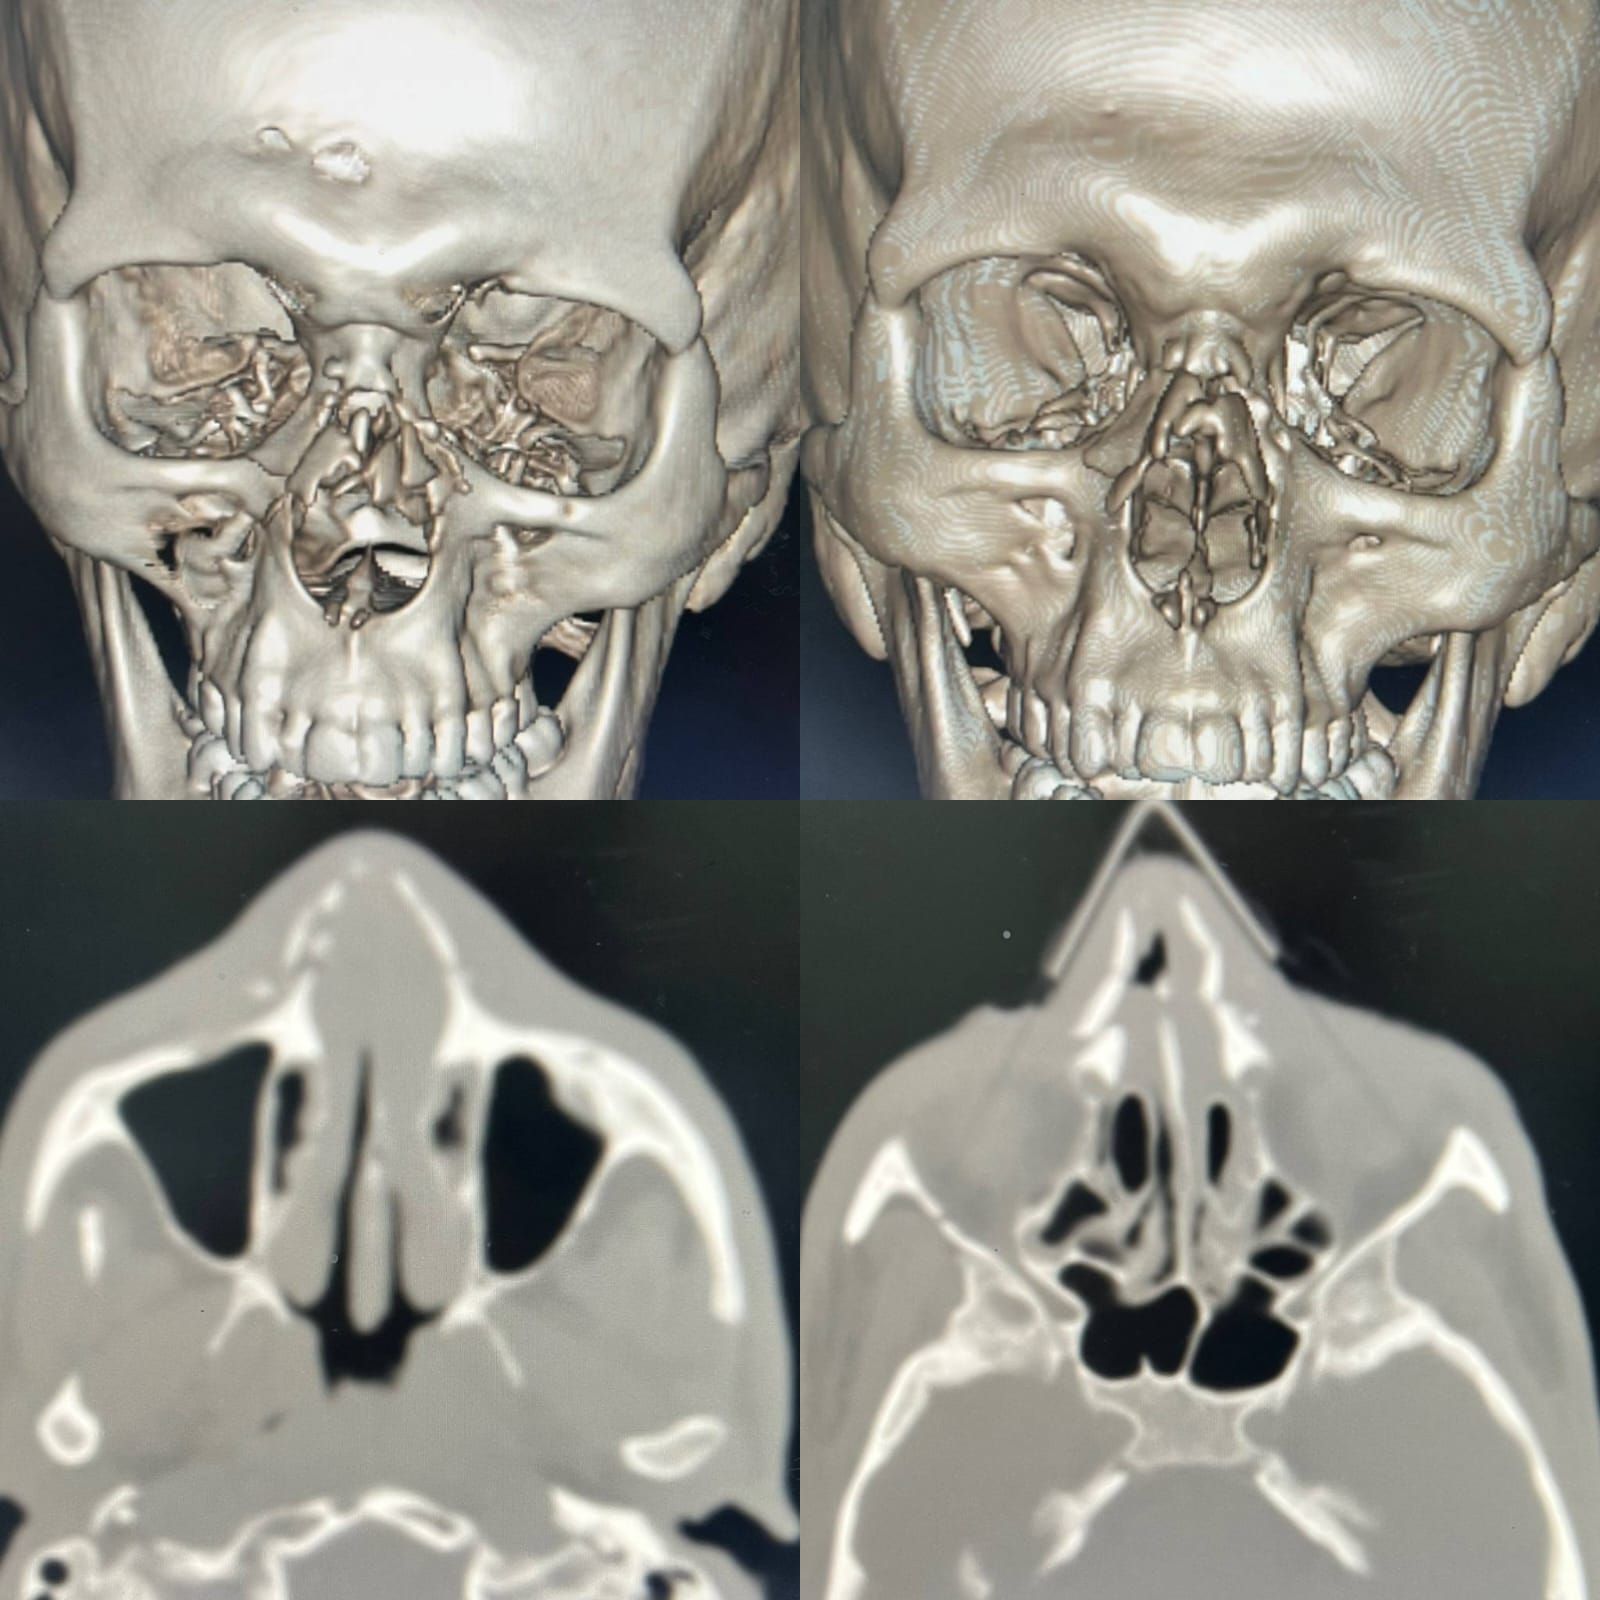

حالة حرجة واستقبال عاجلوأوضح وكيل الوزارة أن المريض وصل إلى قسم الطوارئ في حالة حرجة، حيث تبين وجود تهتك شديد بعظام وأنسجة الوجه، مع تضرر بالغ في معالم الأنف، واندماج بين مجريي التنفس والطعام، ما استدعى تدخلاً طبيًا عاجلًا لإنقاذ حياته.

جراحة معقدة استمرت 5 ساعاتومن جانبه، أوضح الدكتور أحمد معتمد عامر، استشاري ورئيس قسم جراحة الوجه والفكين، أنه تم التعامل مع الحالة بشكل فوري، حيث جرى تأمين مجرى الهواء أولًا، ثم نقل المريض إلى غرفة العمليات لإجراء تدخل جراحي دقيق استمر نحو 5 ساعات متواصلة.

وأشار إلى أن الجراحة تضمنت فك الاندماج بين الفم والأنف، وإعادة بناء المسارات التشريحية الطبيعية، إلى جانب ترميم عظام الأنف والأنسجة الرخوة، بما أسهم في استعادة الشكل التشريحي للوجه، وفصل الوظائف الحيوية المتعلقة بالتنفس والكلام وتناول الطعام.

جانب من تشخيص الحالة